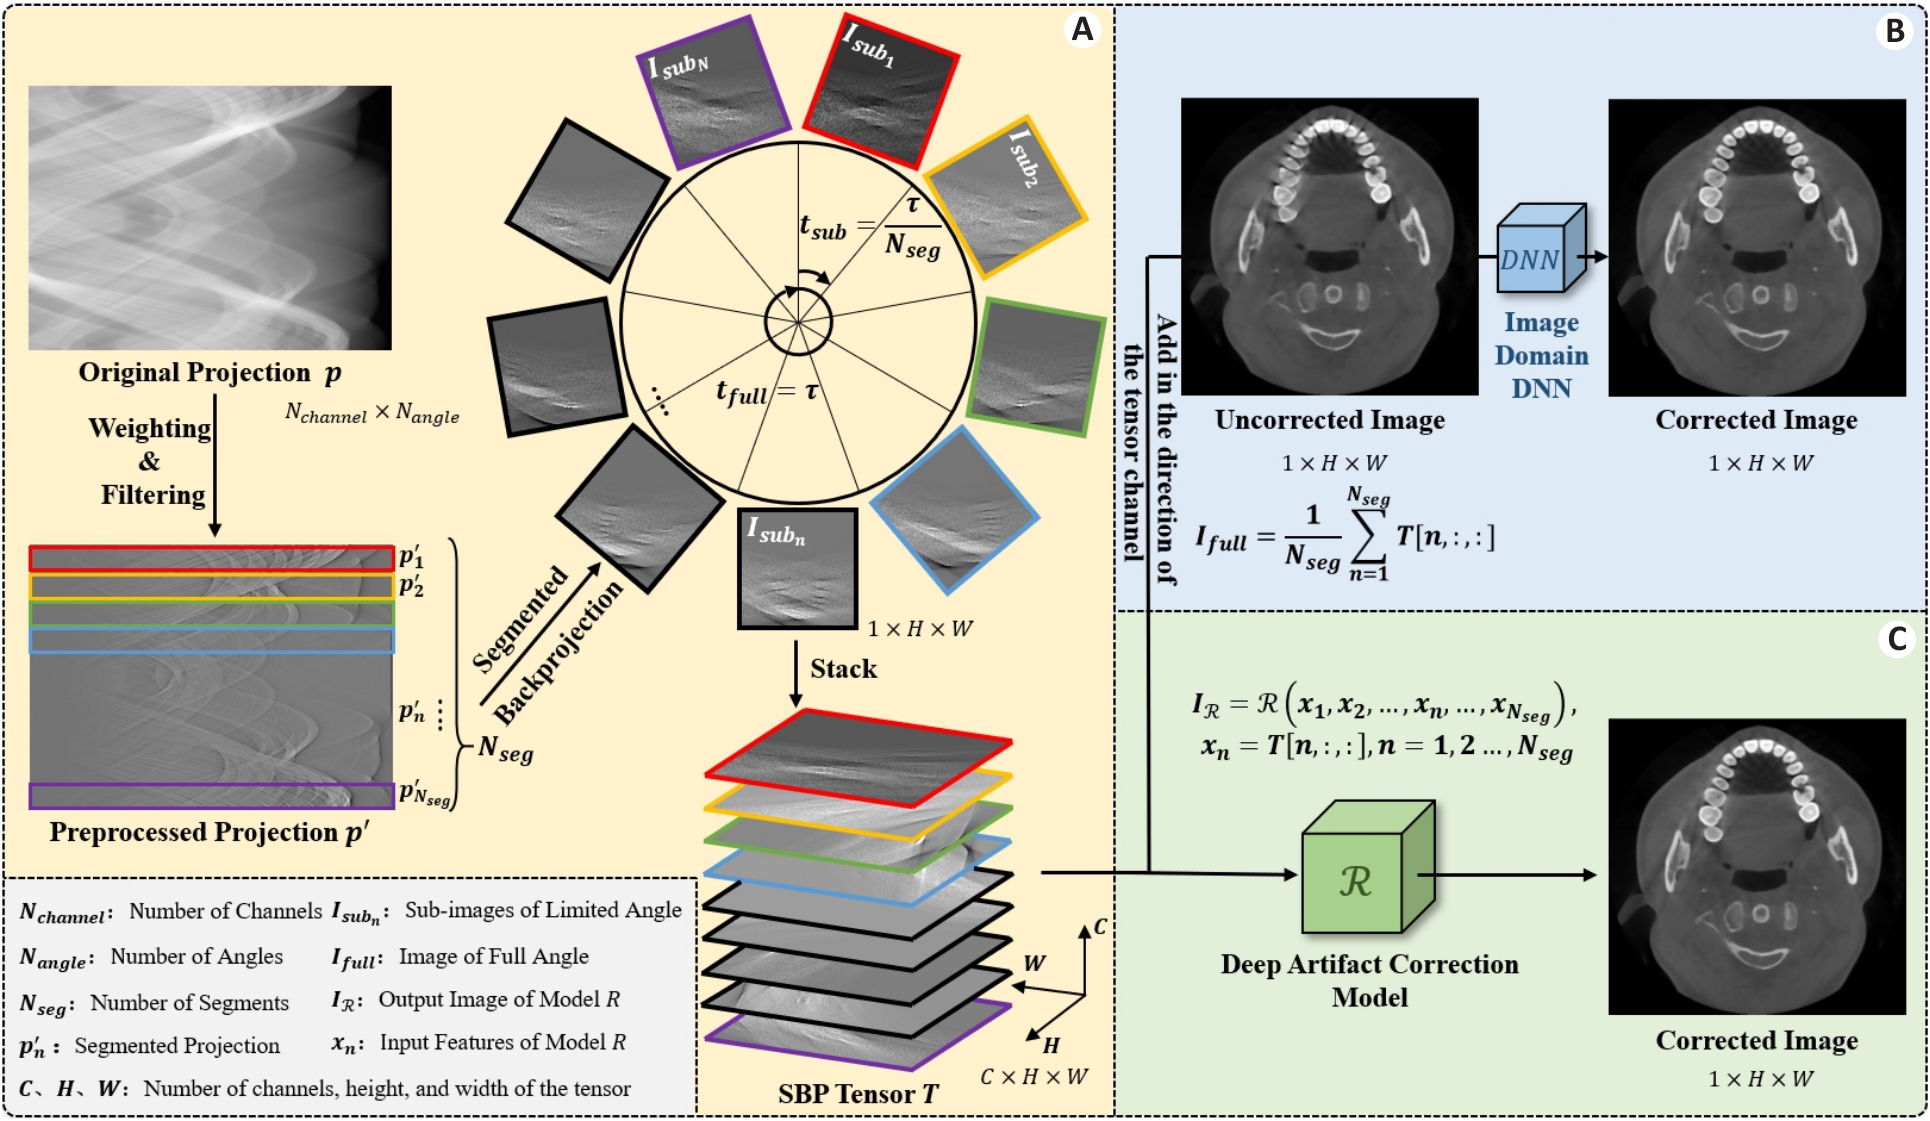

Fig.1 Schematic diagram of the segmented backprojection tensor. A: Origin of the segmented backprojection tensor. B: Training idea of DNN in the traditional image domain. C: Training idea of the proposed model.